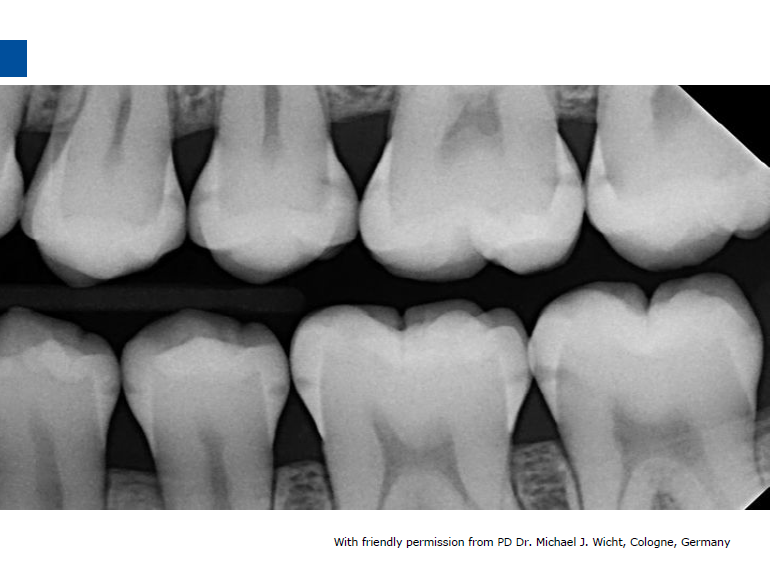

微创牙科治疗是一种全新的龋病治疗理念,着眼于疾病的早发现、早诊断、早治疗。树脂渗透治疗是介于再矿化治疗和充填治疗之间的一种创新的治疗手段,通过微量的去除牙体组织,达到加固脱矿釉质、阻止进一步脱矿的目的。

lcon渗透基于封闭釉质龋空隙的一种特殊树脂的渗透,封闭釉质龋小孔,从而阻断致龋酸传播途径,阻止龋病进一步发展。这种材料操作方法简单,对牙体组织损伤轻微,不用通过麻醉和磨切牙体来达到加固脱矿釉质,同时可以改变釉质龋表面的白色或棕色改变,达到美观修复效果,是对龋病微创治疗的突破。